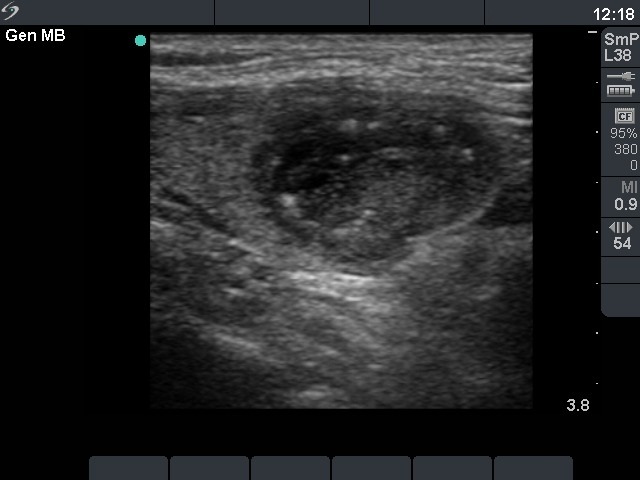

Metastasis of a kidney carcinoma to the thyroid - case 1574 |

Benign hyperplastic nodule (histological diagnosis) - case 1582 |

Both images show one relatively large granule which correspond to punctate echogenic foci.

Parts of the hyperechogenic granules are located in cystic area, while others are found in the solid part of the lesion. The latter might be punctate echogenic foci.